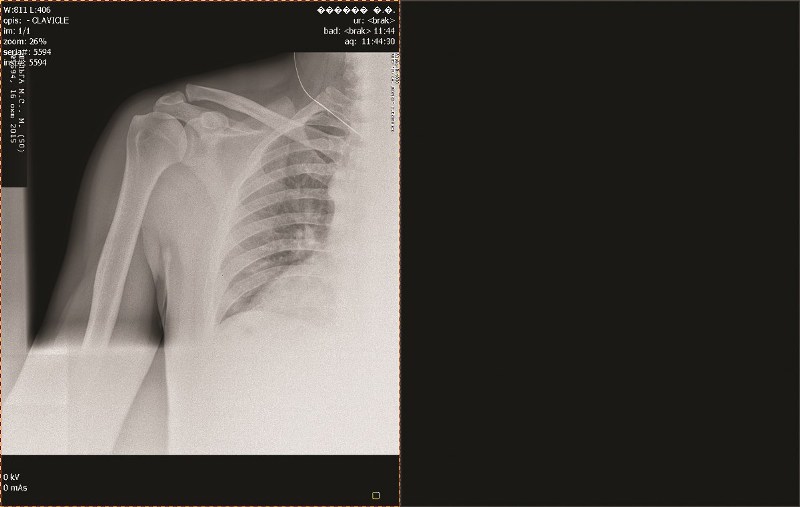

ARTYKUŁ SPONSOROWANY Z lek. med. Markiem Kulczykiem, specjalistą ortopedii i traumatologii narządu ruchu ze Szpitala im. Św. Rodziny w Rudnej Małej, rozmawia Marta Bochenek